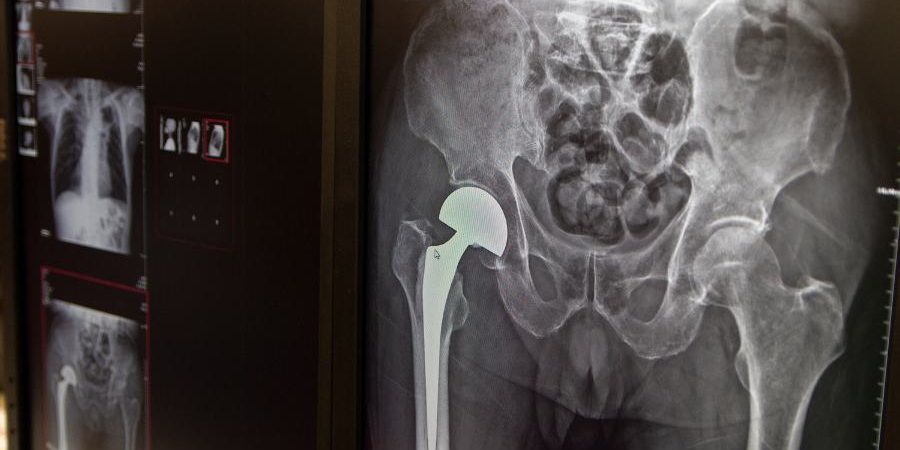

Procedimientos para prótesis de cadera y rodilla

Estas intervenciones quirúrgicas, realizadas bajo anestesia, sustituyen la articulación dañada por componentes artificiales diseñados para replicar su movimiento.

- Cadera: Se reemplaza la cabeza del fémur con una esfera metálica, complementada por una cúpula plástica en la pelvis.

- Rodilla: Los extremos del fémur y la tibia se sustituyen por piezas protésicas, incluyendo la rótula en la mayoría de los casos.

Los materiales utilizados son metales como acero o titanio, combinados con plásticos altamente resistentes al desgaste. Las prótesis pueden fijarse al hueso con cemento o mediante anclaje directo.